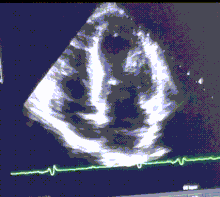

Athlete's heart is usually an incidental finding during a routine screening or during tests for other medical issues. An enlarged heart can be seen at echocardiography or sometimes on a chest X-ray. Similarities at presentation between athlete's heart and clinically relevant cardiac problems may prompt electrocardiography (ECG) and exercise cardiac stress tests. The ECG can detect sinus bradycardia, a resting heart rate of fewer than 60 beats per minute. This is often accompanied by sinus arrhythmia. The pulse of a person with athlete's heart can sometimes be irregular while at rest, but usually returns to normal after exercise begins.[12][13][14]

- Echocardiography – differentiation between physiological and pathological increases of the heart's size is possible, especially by estimating the mass of the wall (not over 130 g/m2) and its end diastolic diameter (not much less 60 mm) of the left ventricle.[9][23]